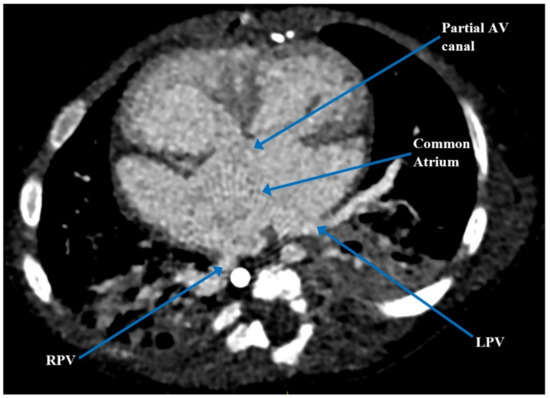

| Present case [6] | Heterotaxy syndrome with partial LPA sling, partial AV canal with a common atrium, atrial situs ambiguous, interrupted IVC, VSD, and PDA | 5 months | PDA occlusion, clipping and division of the anomalous LPA | Defined complex anatomy and surgical plan for biventricular repair | Biventricular repair |